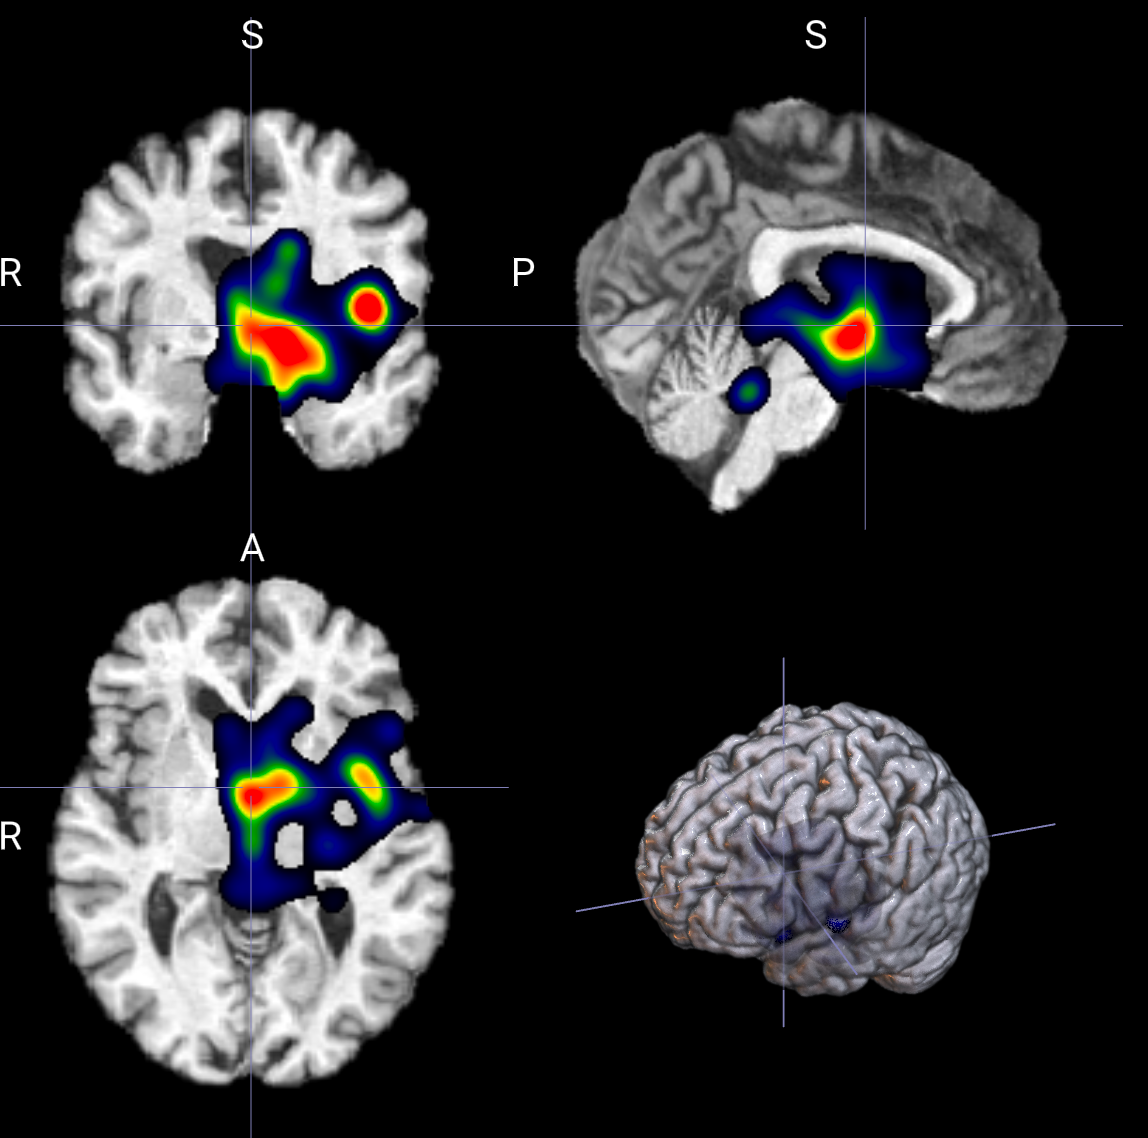

输出示例